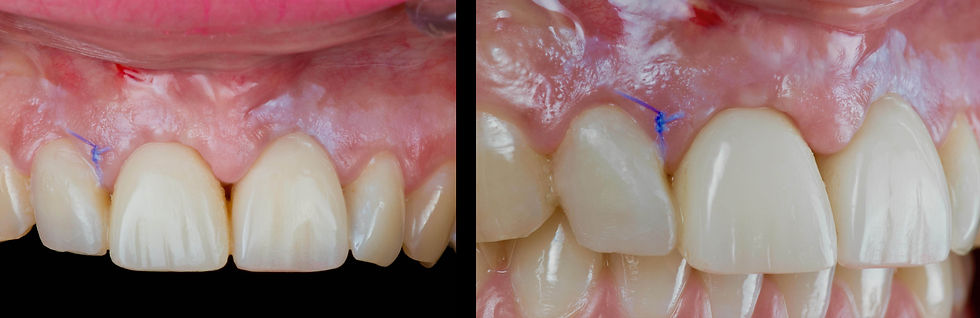

Clinical pictures 7 days after surgery: the sutures are removed.

Clinical picture 30 days after surgery: the tissues are healthy and well supported, even if they are not mature yet.